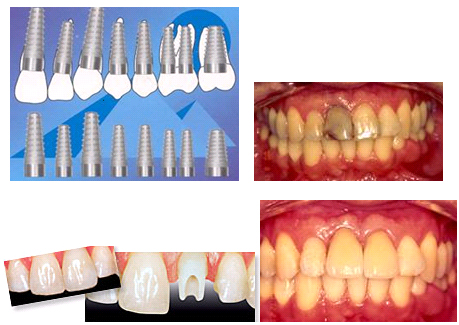

A dental implant is an artificial screw like object placed into your jaw to maintain bone structure and also used to support crowns and bridges. Dental implants are an ideal option for patients with good general oral health and who have lost a tooth or teeth due to periodontal disease, injury, or some other reason.

Dental implants are high-tech in nature; they are actually used more as a non invasive technique to replace missing teeth, avoiding the traditional bridgework or the use of removable prostheses. Implants avoid the neighboring teeth by not relying on them as in traditional procedures like the ones mentioned above.

Are there different types of implants?

Yes today there are two different types of implants. The endosteal (in the bone), which is the most commonly used type of implant. The different types include screws, cylinders or blades which are surgically placed into the jaw bone. Implants like this are usually used as an alternative for patients that need bridges or are using removable prostheses. Then we have also the subperiosteal (on the bone). These implants are placed on the top of the jaw with the metal framework’s posts protruding trough the gum to hold the prostheses. This option is an ideal solution for patients who are unable to wear conventional dentures and who have lost the necessary supporting bone for the other type of implant mentioned above.

Mini-implants are a new type of implant that we offer in our office offer with a very good prognosis to support complete dentures or in some cases partial dentures. These mini-implants can be used also as middle abutments for some long fixed bridges when more than one tooth is missing. By using this technique the implant takes the pressure off the natural teeth that are supporting the bridge.

Once we establish that you are qualified for implants you need a special X-Ray that will determine if you have enough bone structure that will support the implants. Next we may need to take some impressions of your mouth and probably some pictures. Once we have all of this information we will go over your case with an oral surgeon and periodontist to ensure that we can give you the best possible options. When every detail has been discussed, our team will need to sit down with you to discuss your specific treatment options.